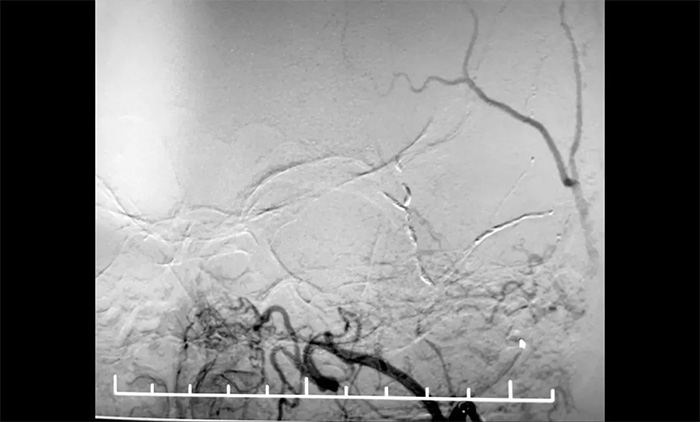

12月29日,顺利进行手术。术中,王贵平博士在介入团队协助下克服血管迂曲的困难,导管精准到达左脑膜中动脉前支、左脑膜中动脉后支,之后缓慢注入液体栓塞剂,栓塞剂逐渐向脑膜中动脉主干反流,复查造影,左脑膜中动脉无明显前向血流,手术成功。术后,患者无新发神经功能缺损。言语不清,肢体活动不利,头晕等症状逐步好转。

▲ 顺利栓塞脑膜中动脉